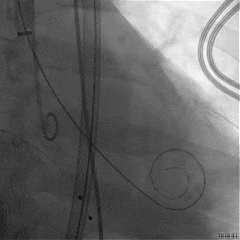

TAVR手术过程

主动脉瓣大量反流

回撤导引鞘,定位键顺利展开

输送器调弯

定位键解离

推送入窦形态改变不明显

无窦瓣叶脱垂影响瓣叶夹持

回撤后增加调弯夹持瓣叶

右窦中心造影确认瓣叶夹持

食道超声确认瓣叶夹持

经胸超声确认右冠瓣叶夹持

回撤MP导管,一键释放瓣膜

松弯后输送器回撤至大鞘,更换小鞘

术后右窦中心造影,无漏,无AVB